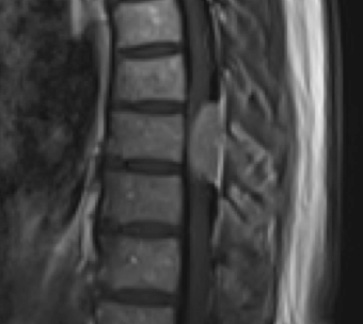

Postoperative MRI T1w demonstrating interval resection with cord re-expansion (blue arrow)

Postoperative MRI T2 illustrating the restoration of CSF surrounding the cord (blue arrow)